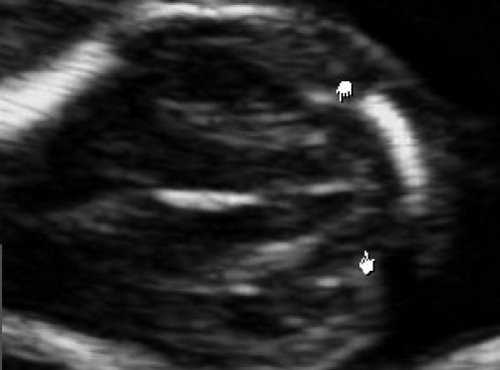

Как сказано выше, имеет значение и измерение ножек "осьминожки", так среднее значение диаметра нижней ножки, т.е. IV желудочка в зависимости от КТР в срок 11-14 недель варьирует от 1,5 до 2,5 мм (рис. 4).

Рис. 4. Измерение и взаимоотношение ножек "осьминожки" - ствола мозга и IV желудочка у плода, беременность 12 недель.

Измерение ножек "осьминожки".

Красный цвет - диэнцефалон (таламус), со стволом мозга (верхняя ножка) и IV желудочком (нижняя ножка); желтый цвет - большая цистерна головного мозга; синий цвет - воротниковое пространство.